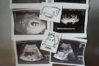

Ikasa a tu widać jak rośnie nasze Crio-szczęście

To może coś w tym jest,że jak organizm był przygotowany wtedy, to następnym razem mu łatwiej.Dbaj o siebie teraz i o maluszka!!!Ikasa a tu widać jak rośnie nasze Crio-szczęście